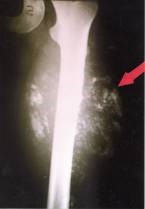

Wir sehen links im Röntgenbild, dass sich eine callushaltige Manschette um den osteolytischen Teil des Knochens gelegt hat. Der Callus ist also nicht, wie man vermuten könnte, in Richtung des geringsten Widerstandes ausgelaufen, sondern er ist sinn- und planvoll um den ganzen Knochen herumgelaufen, um diesen Knochenabschnitt zu stabilisieren.

Der Callus läuft also nicht, wie wir früher geglaubt hatten, „irgendwohin“, sondern er wird vom Organismus zirkulär in Form einer Manschette um den Knochen herumgeführt, so dass am Ende eine zirkuläre Stabilisation des Knochens resultiert.